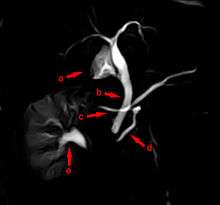

The most common and accurate way of diagnosing an individual with this anomaly is by MRCP (Magnetic Resonance Cholangiopancreatography) or ERCP (Endoscopic Retrograde Cholangiopancreatography). This test can demonstrate the presence of two separately draining ducts within the pancreas. Other tests can assist doctors with diagnosis, such as a CT scan and an MRI.